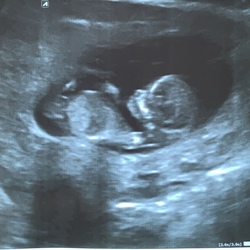

Ik heb wel over de niche gelezen, maar kunnen ze dat zo makkelijk even checken met een inwendige echo? Ik heb verder geen spotting ofzo, cyclus is weer op gang ook. De pijn is aan/in de gehele wond.. Maar als m'n pijn nog lang aanhoudt ga ik navraag doen. Hoewel er dus velen zijn die dit voelen..